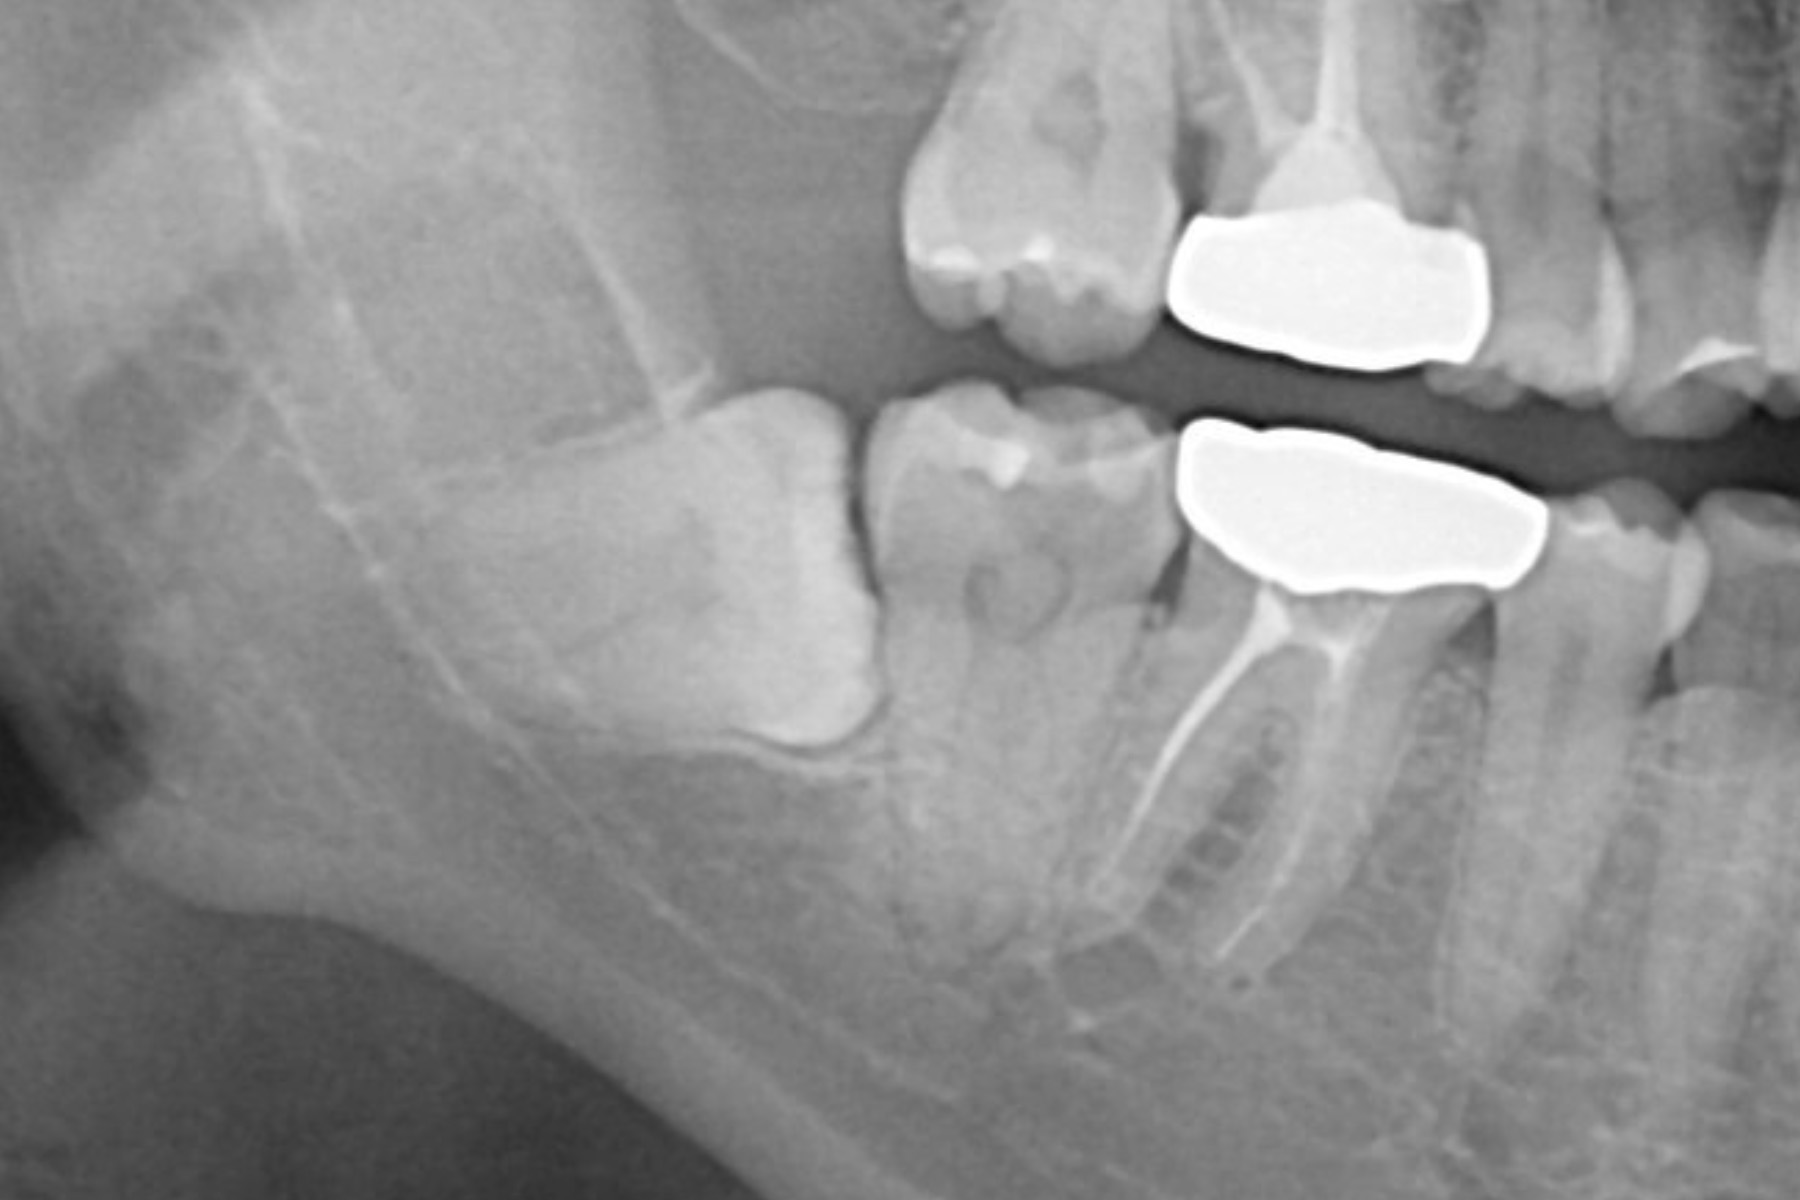

CASE23:親知らずを使用した歯の移植の症例

CASE23